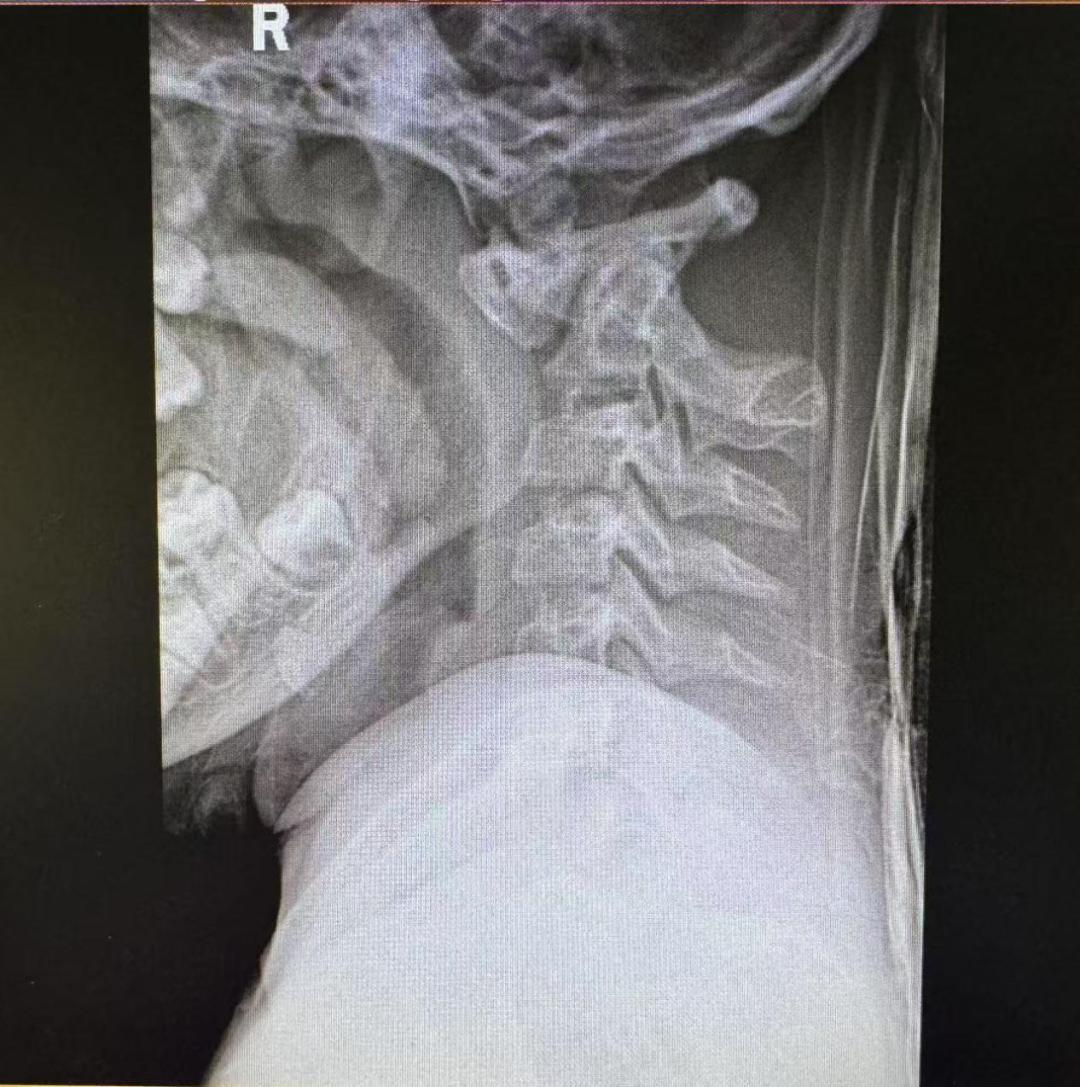

术前术后颈椎X光片

经院方详细检查后,王亮主任团队发现,乐乐的寰枢椎脱位是由游离齿突引起。虽然从影像学上看没有明显的复位障碍,适合进行后路复位固定手术,但在进一步的颈椎CT检查后,王亮主任团队却发现了棘手的问题:患儿异常细小的颈椎解剖结构使得手术置钉难度倍增。

为解决这个问题,脊柱外科一科主任王亮在术前采用3D打印技术复刻了乐乐的寰枢椎模型,反复进行充分的手术模拟。几次模拟下来,王亮有了信心,决定直接实施颈椎后路手术复位手术。术中,团队紧密配合,将手术精度控制在“毫米级”,一次性精准置钉,完成寰枢椎复位与固定。